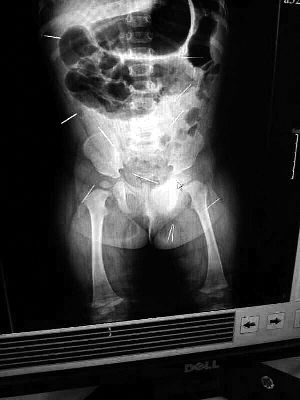

山東聊城11個月女嬰萱萱(化名)疑似被人以12根鋼針插滿臀部、腹腔等部位,昨天在兒童醫(yī)院會診后,醫(yī)生稱3根針靠近胸腔最危險,首批先行取出,預計將在下周二手術。孩子父母稱孩子一直由家人照顧,自家與他人并無冤怨。山東警方表示正在偵破中,不便透露案情。

“要不是當初那幾個紅點,可能到現(xiàn)在我們還不知道孩子身體里有鋼針!”昨天,在兒童醫(yī)院住院處,萱萱爸爸范先生稱,日前原本很愛笑的萱萱突然變得有些焦躁,一抱起來就哭,孩子母親偶然間在萱萱屁股上發(fā)現(xiàn)了幾個小紅點兒,原以為是蚊蟲叮咬,就醫(yī)結果卻讓人不寒而栗。“醫(yī)院拍出的片子上,萱萱的體內(nèi)有12根鋼針,插滿臀部、腹腔、骨盆等各個部位。”范先生介紹,因為鋼針已深入體內(nèi),要是孩子不哭鬧,他們很難發(fā)現(xiàn)。

北京晨報記者了解到,目前體內(nèi)的12根鋼針多分布在孩子的臀部,一根在腹部,其余3根在胸腔附近,其中一根很接近心臟?!耙驗楹⒆犹?,醫(yī)生們害怕取針的時候對她造成傷害,在胸腔附近的3針可能會威脅她的生命”。